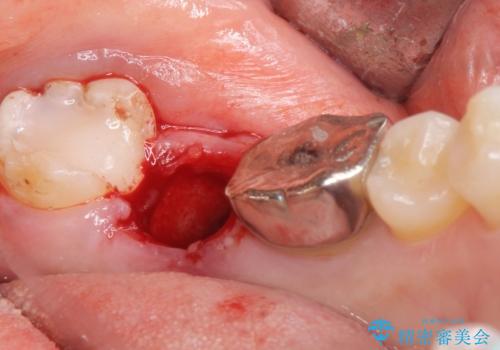

左下の奥歯(左下7)は破折しており保存不可能な状態でした。

ご希望により、隣の親知らず(左下8)を移植しました。